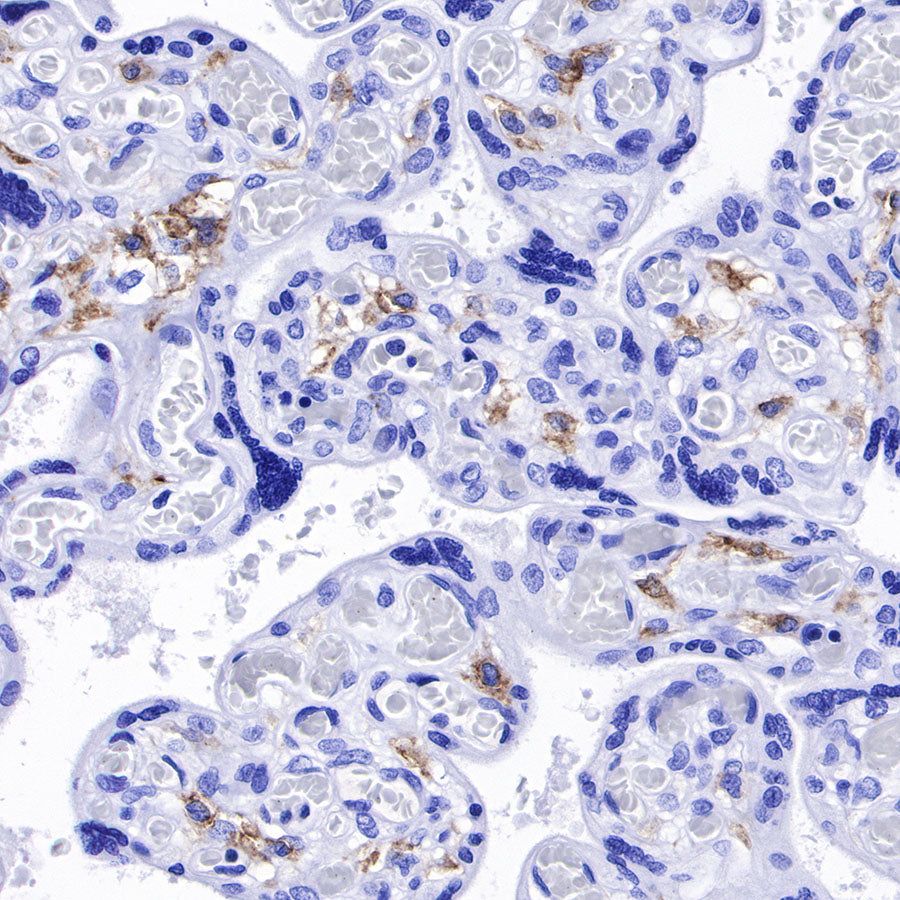

IHC shows positive staining in paraffin-embedded human placenta. Anti-CD169 antibody was used at 1/250 dilution, followed by a HRP Polymer for Mouse & Rabbit IgG (ready to use). Counterstained with hematoxylin. Heat mediated antigen retrieval with Tris/EDTA buffer pH9.0 was performed before commencing with IHC staining protocol.